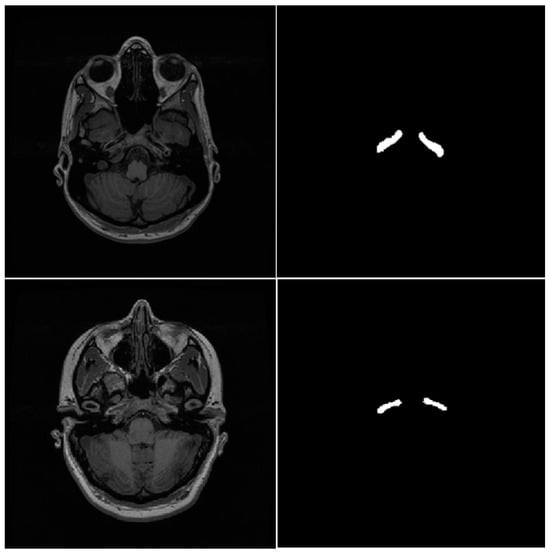

A 2.5D Self-Training Strategy for Carotid Artery Segmentation in T1-Weighted Brain Magnetic Resonance Images

3.1. Datasets

3.2. Preprocessing and Data Augmentation